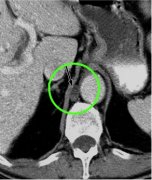

胸导管CT(CT of thoracic duct) 80 Patients Thoracic Duct (TD) visible: - Lower segment 81% - Middle segment 54% - Upper segment 69% - Arch of TD 57% Schnyder, P et al. Eur J Radiol 1983;3:18-23 乳糜池 Cisterna Chyli Pinto, P. S. et al. Ra...